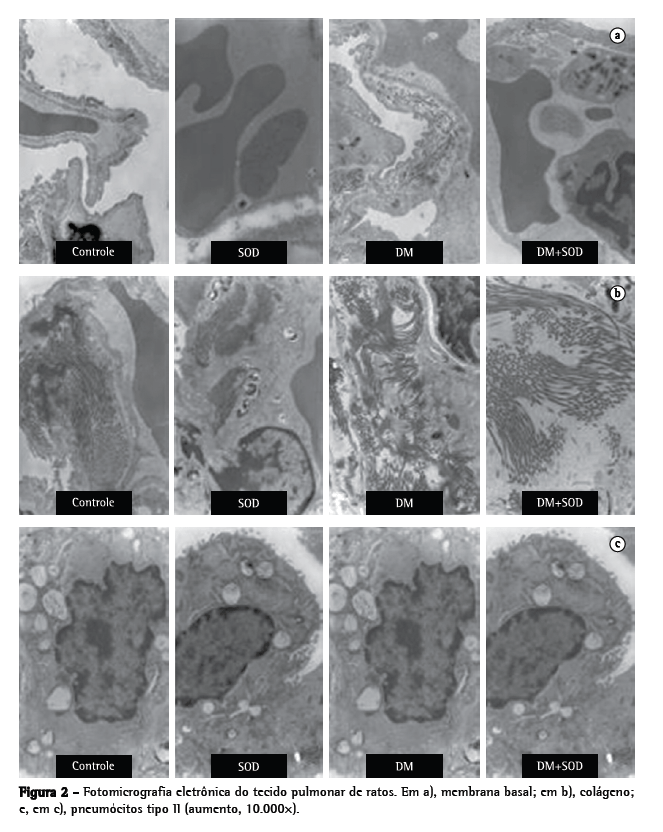

A análise ultraestrutural do tecido pulmonar dos animais do grupo DM mostrou espessamento da membrana basal, fibrose do interstício pulmonar, desorganização dos pneumócitos tipo II e ausência de corpos lamelares, sugerindo que a produção de surfactante foi reduzida nos animais do grupo DM (Figura 2). Essas alterações não foram significativas nos grupos controle e SOD, enquanto houve uma redução da espessura da membrana basal no grupo DM+SOD, o que foi semelhante aos resultados obtidos para os grupos controle e SOD.

Quando os pneumócitos tipo II foram analisados, observou-se que os animais do grupo DM+SOD apresentavam corpos lamelares.

Em nosso estudo, observamos que os ratos com DM induzido por estreptozotocina apresentaram alterações na ultraestrutura do tecido pulmonar, avaliada por microscopia eletrônica, tais como aumento da espessura da membrana basal, aumento da fibrose pulmonar e alterações nos pneumócitos tipo II. Após esses ratos terem sido tratados com SOD, a ultraestrutura do tecido pulmonar retornou a condições quase basais.